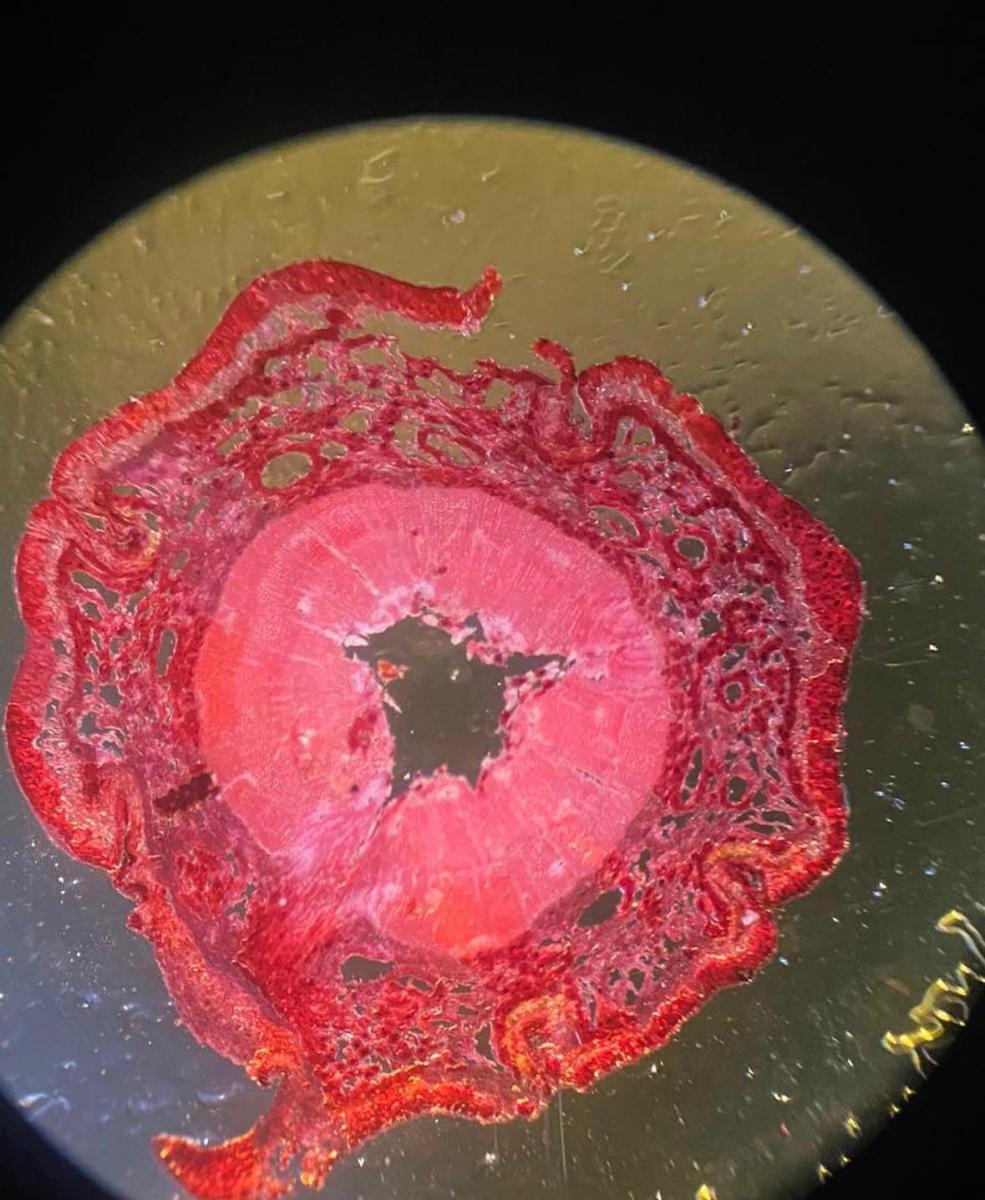

1. Bakteriyaları “ram edəcək”, xərçəng və siyənəyi disseksiya edəcək, siçovulların sosial davranışını öyrənəcək və DNT molekullarını ayıraraq onların necə işlədiyini anlayacaq.

2. Həqiqi avadanlıq üzərində mikroskopiya və disseksiya bacarıqları qazanacaq — biologiya fakültəsinin birinci kurs tələbəsindən heç də geri qalmayacaq.